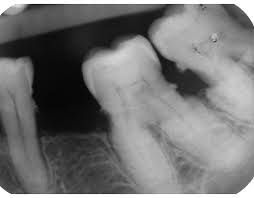

Hypercementosis is an idiopathic, non-neoplastic condition characterized by the excessive buildup of normal cementum (calcified tissue) on the roots of one or more teeth. A thicker layer of cementum can give the tooth an enlarged appearance, which mainly occurs at the apex or apices of the tooth.